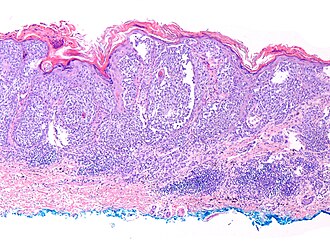

|

Malignant melanoma. H&E stain. | |